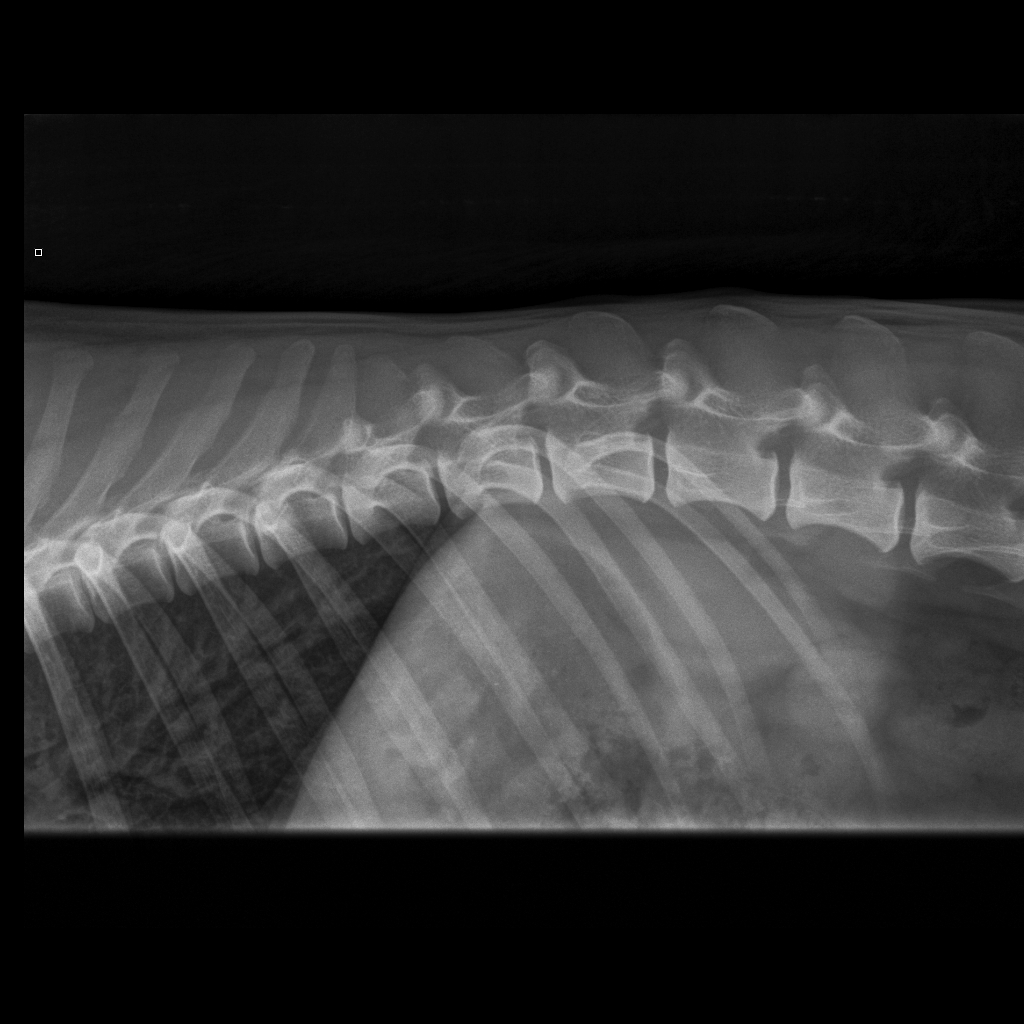

Viralliset selkäkuvat

Välimuotoinen lanne-ristinikama: LTV0 (normaali)

Selän spondyloosi: SP0 (puhdas)

Nikamien epämuotoisuus: VA0 (normaali)

(1/16)

(6/14)

Selän spondyloosi: SP3 (aste 3, keskivaikea)

(7/13)

rintaranka,

lanneranka